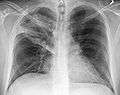

| A chest X-ray showing a very prominent wedge-shape bacterial pneumonia in the right lung. | |

- Normal AP CXR

Normal lateral CXR